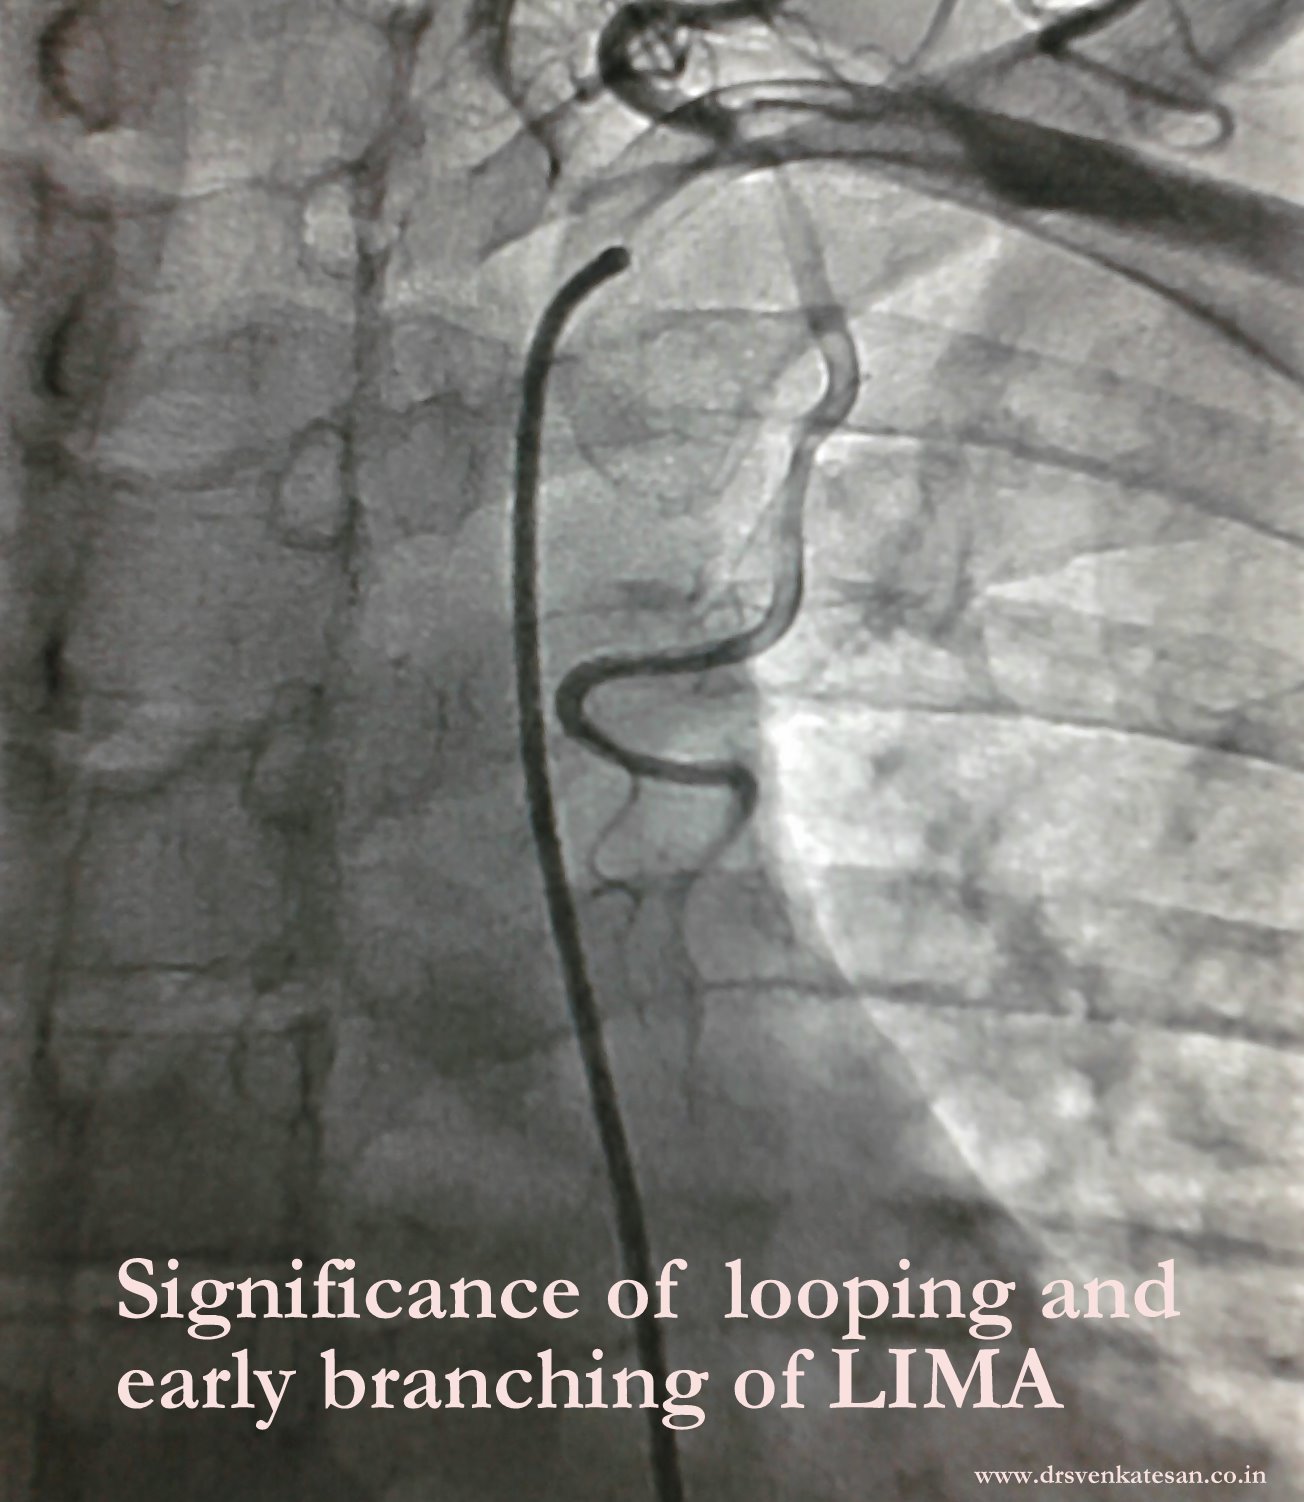

I recently came across an unusual LIMA  arterial  branching pattern .

Random thoughts

• A naturally dividing LIMA faciliates multiple sequential grafting of LAD or diagonal branches.

• As branches steal the LIMA flow it is not good for the patient

• Surgeons struggle to clip the branches.

• A branching LIMA has tendency to have  small diameter (As in the above patient )

I need a surgeons Input here.

Looping of LIMA is rarely an issue in hemodynamic point of view. But some  believe  a looped up LIMA is slightly prone for graft disease.Complex looping are reported rarely.

A loop and a early branch of LIMA : What is the implication ?

Abnormal  or premature branching pattern  of LIMA  needs clipping as it may divert blood supply to LAD.Terminal branches can be used as a sequential graft to a branch of LAD  usually a diagonal. In spite of all these issues , LIMA is  rarely unsuitable either anatomically or physiologically .It is a safest vessel to graft.